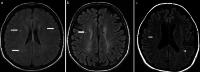

The recently developed effective treatment of primary progressive multiple sclerosis (PPMS) requires the accurate diagnosis of patients with this type of disease. Currently, the diagnosis of PPMS is based on the 2017 McDonald criteria, although the contribution of magnetic resonance imaging (MRI) to this process is fundamental. PPMS, one of the clinical types of MS, represents 10%-15% of all MS patients. Compared to relapsing-remitting MS (RRMS), PPMS differs in terms of pathology, clinical presentation and MRI features. Regarding conventional MRI, focal lesions on T2-weighted images and acute inflammatory lesions with contrast enhancement are less common in PPMS than in RRMS. On the other hand, MRI features of chronic inflammation, such as slowly evolving/expanding lesions (SELs) and leptomeningeal enhancement (LME), and brain and spinal cord atrophy are more common MRI characteristics in PPMS than RRMS. Nonconventional MRI also shows differences in subtle white and grey matter damage between PPMS and other clinical types of disease. In this review, we present separate diagnostic criteria, conventional and nonconventional MRI specificity for PPMS, which may support and simplify the diagnosis of this type of MS in daily clinical practice.